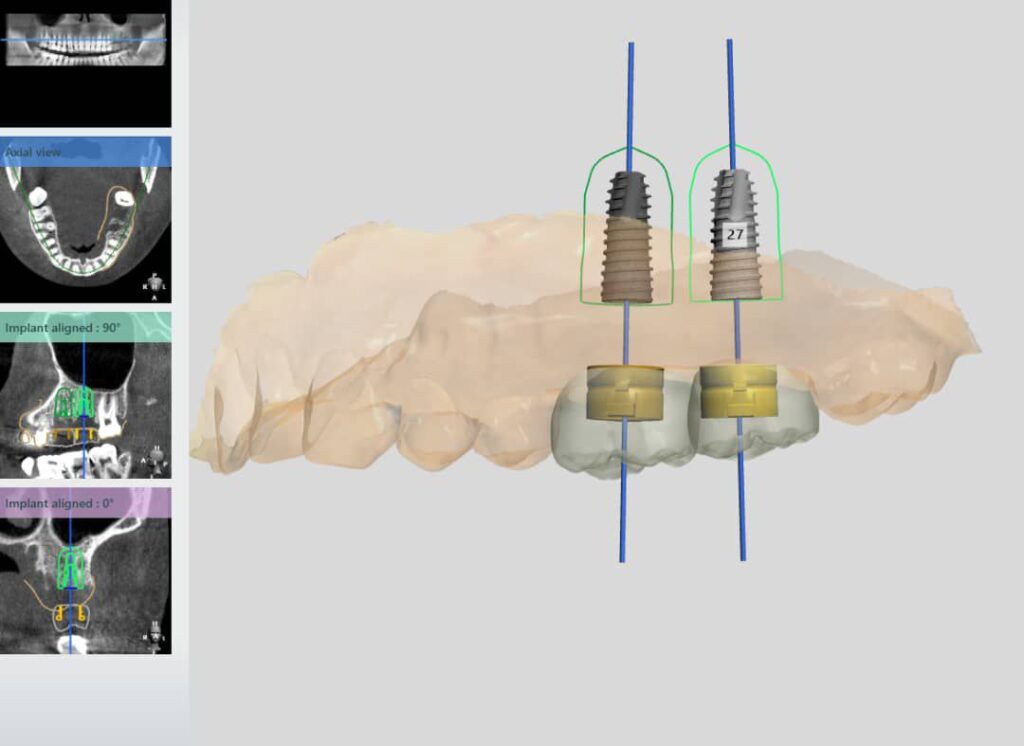

تصویربرداری سه بعدی( CBCT):

اسکن سه بعدی فک و دندان ها انجام میشود تا ساختارهای دقیق استخوان و موقعیت عصب ها مشخص شود

طراحی دیجیتال:

با استفاده از نرمافزارهای پیشرفته، محل قرارگیری دقیق ایمپلنت طراحی و شبیه سازی میشود

ساخت راهنمای جراحی( Guide surgical):

با پرینتر سه بعدی ابزار خاصی تولید میشود که به جراح کمک میکند ایمپلنت را با دقت بسیار بالا در جایگاه مناسب قرار دهد

کاشت ایمپلنت:

عمل جراحی با استفاده از راهنمای جراحی و دستگاههای دیجیتال انجام میشود

تاج دندان نیز با دستگاههای CAD/CAMطراحی و ساخته میشود